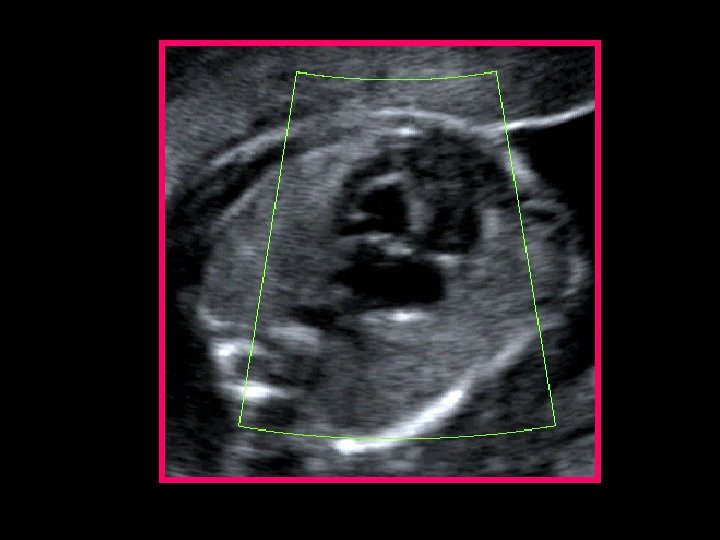

1) Bidimensionale: scansione “ 4 camere” Discrepanza fra i due ventricoli Predominanza o Ventricolo sinistro frequent. piccolissimo (stenosi mitralica e aortica) o Ventricolo dx virtuale ( atresia di mitrale e aorta) (d. d. cuore univentricolare) o Fibroelastosi endocardica ventricolo sinistro (linea iperecogena margine interno VS) o Il VS non raggiunge mai l’apice cardiaco!!! o Valvola mitralica atresica o con anulus ipoplasico o Valvola aortica lembi ipomobili (stenosi) o fissi (atresia). Di solito iperecogenicià dei lembi

Bidimensionale: scansione 4 camere normale HLHS

… Ricapitolando… (a) At 22 weeks’ gestation, on the 4 -chamber view, the severe hypoplasia of the left ventricle, transformed into a virtual cavity due to the mitral atresia (arrowhead) is evident (b) At 32 weeks’ gestation, there is severe hypoplasia of the left ventricle, which is slit-like (arrowhead). (c) In the same case as in (a), color Doppler demonstrates the mitral atresia (absence of left ventricular filling). (d) On the 3 -vessel view, the reverse flow across the hypoplastic aortic arch (in red, arrowhead) (associated tubular hypoplasia) confirms the aortic atresia.